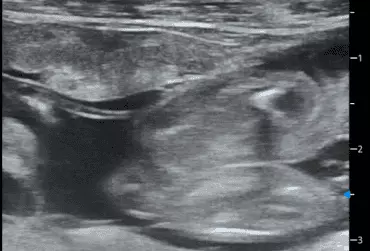

W literaturze opisano niewiele przypadków ciąż bliźniaczych jednokosmówkowych u suk. W trakcie wczesnej diagnostyki ultrasonograficznej ciąży u suki rasy whippet (chart angielski) zobrazowano pęcherz ciążowy, w którym znajdowały się dwa zarodki. Podczas badań kontrol­nych zarodki, a później płody wykazywały prawidłową organogenezę i żywotność. Ich rozwój przebiegał podobnie względem pozostałych ośmiu płodów. W 63. dniu ciąży wykonano zabieg cesarskiego cięcia i wydobyto dwa płody tej samej płci, o bardzo podobnym wyglądzie, z dwóch pęcherzy płodowych przyczepionych do jednego łożyska, oraz pozostałe osiem płodów.